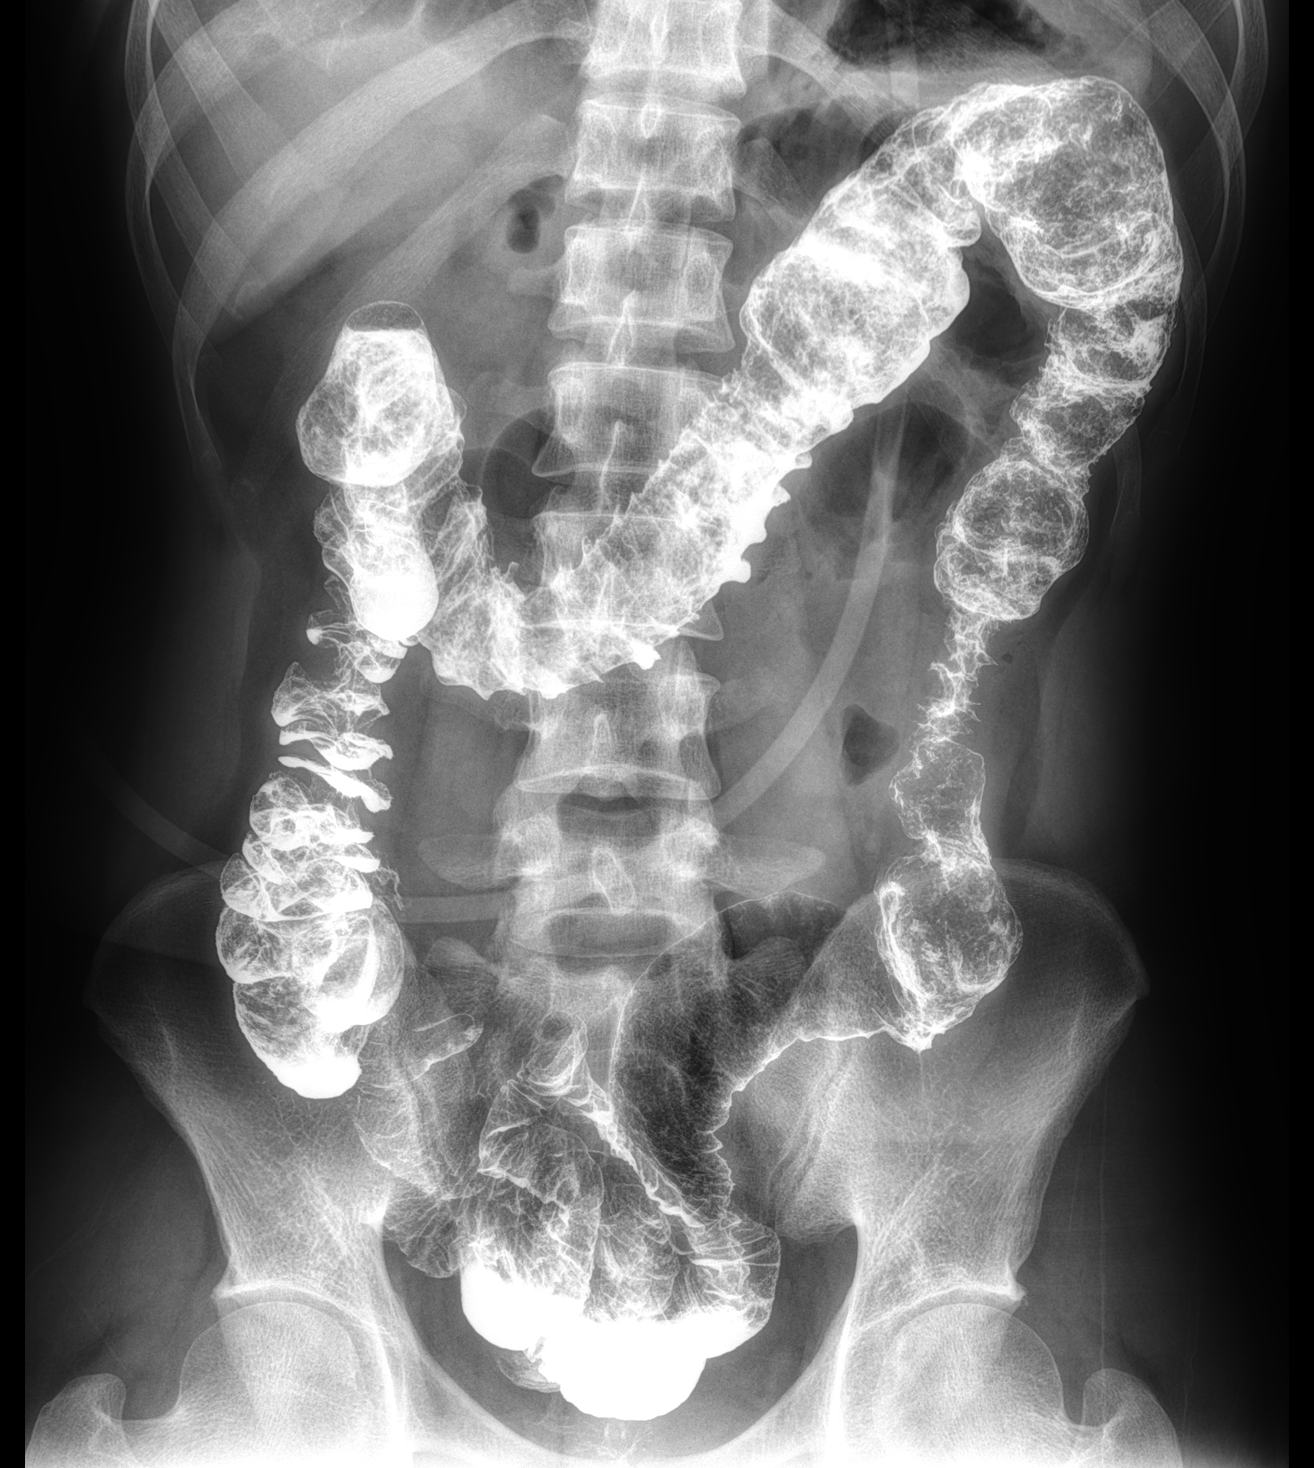

平板探测器

超大尺寸

超范围

超高像素

高清点片

DFP

同步曝光